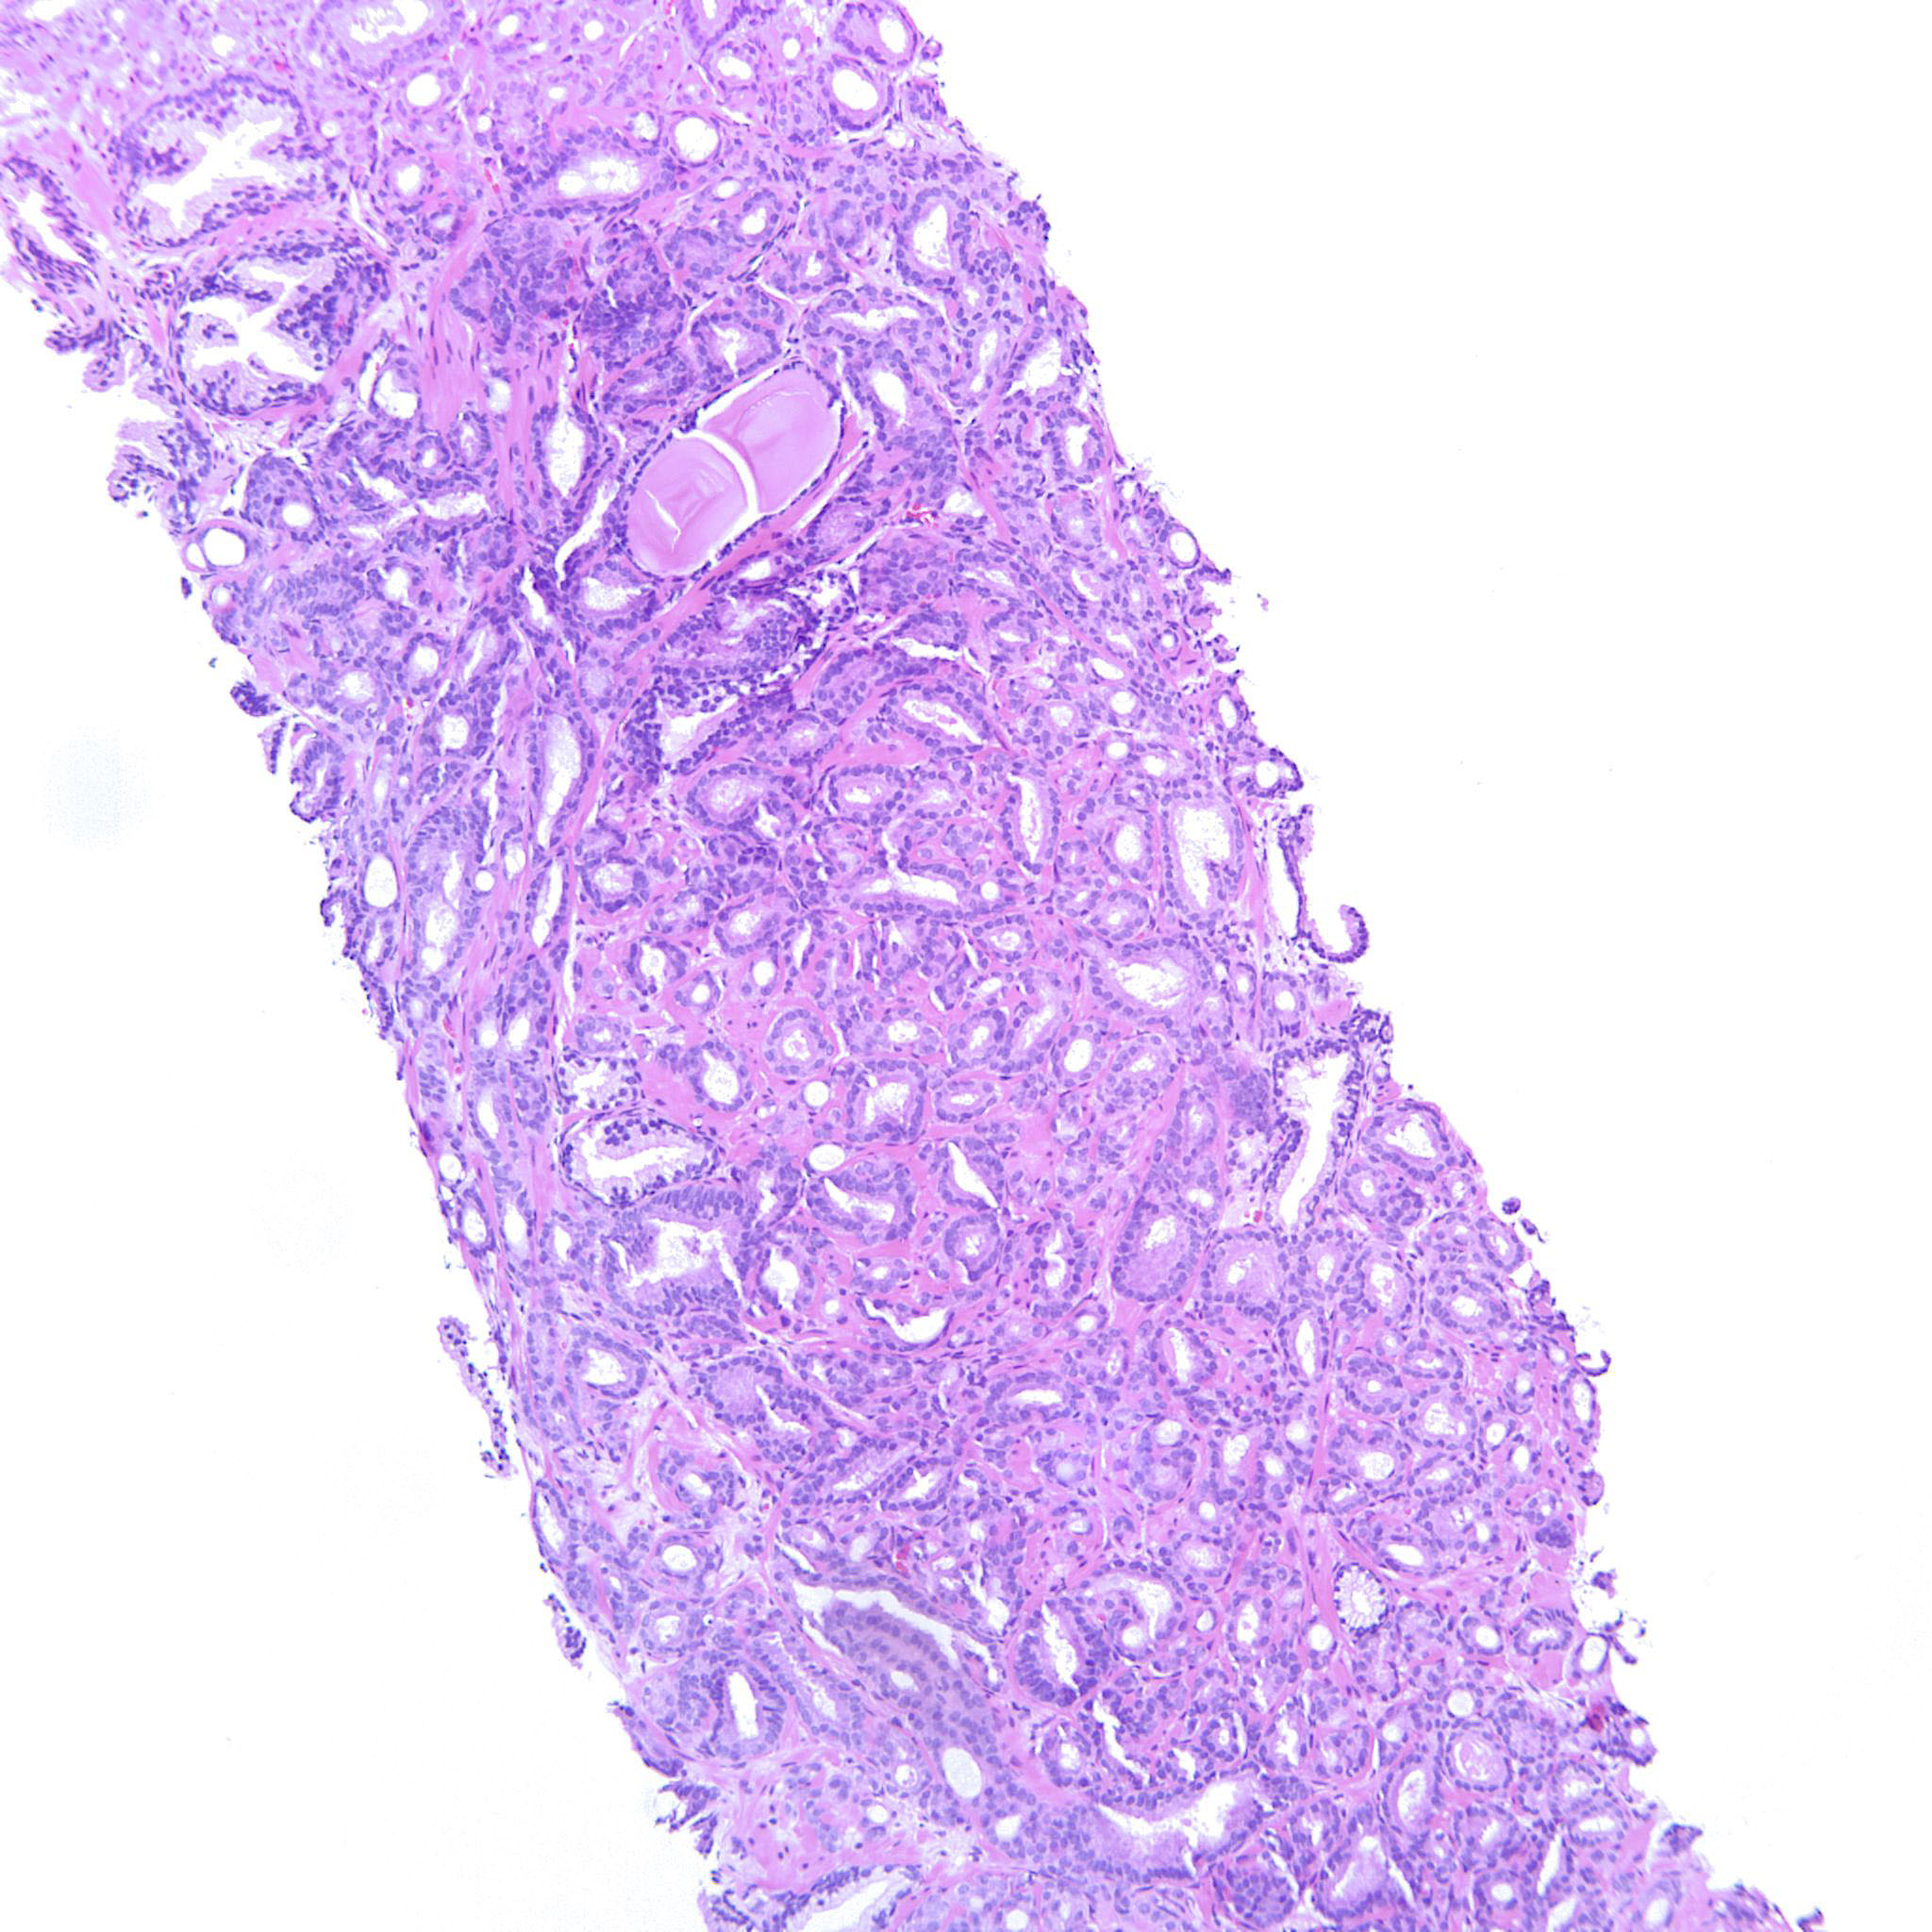

Prostate cancer grading

Case ID: 214